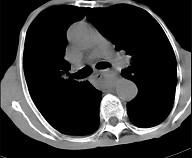

问题 女,71岁,进食时有梗阻感,进行性加重半年,影像检查如图,最可能的诊断是 ( )

选项 A.贲门失弛缓症 B.食管癌并纵隔淋巴结转移 C.食管良性狭窄 D.反流性食管炎 E.食管静脉曲张

答案 B